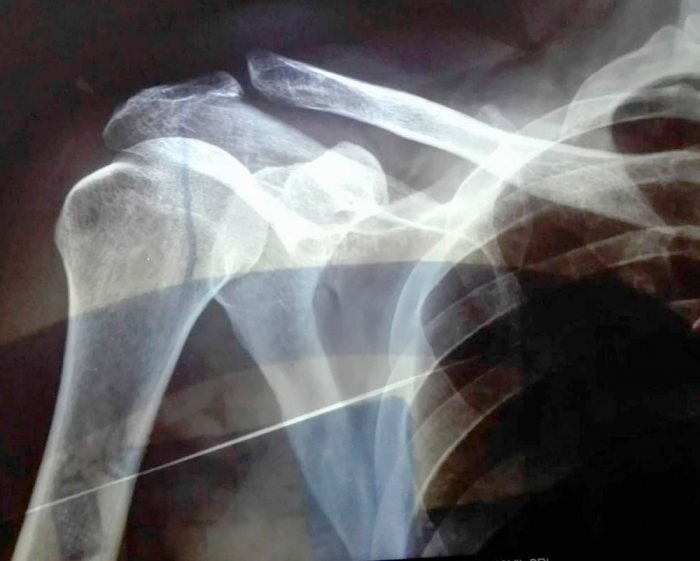

El saldo de la tortura que Juan recibió por efectivos militares, de la Policía, inclusive de los investigadores del caso, son tres costillas rotas, ambos hombros dislocados, el tórax lesionado, las manos con los nervios destrozados y profundos dolores en el ombligo.